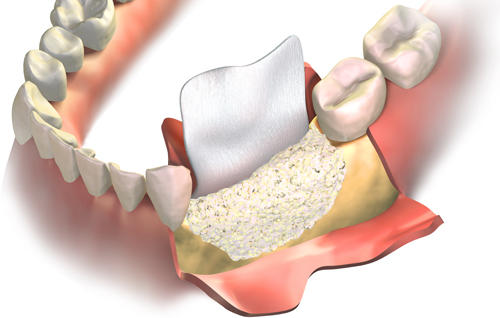

Regeneración ósea del maxilar.

Existen casos en los que inicialmente no se pueden colocar implantes porque no hay hueso suficiente. Para estos casos es necesario aumentar la altura o la anchura del hueso existente para su colocación.

En la Clínica Dental ECCO aplicamos técnicas quirúrgicas de regeneración ósea previa a la colocación de los implantes: injertos óseos, obtención de plasma rico en factores de crecimiento, preservación alveolar y elevación de senos maxilares.

infografía explicativa de refeneración ósea